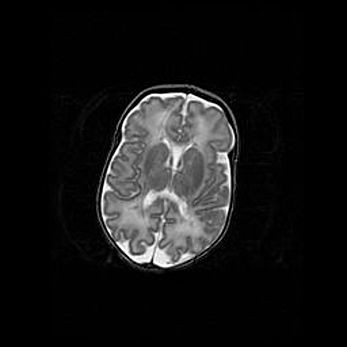

Аномалия Денди-Уокера. Признаки гипоплазии мозолистого тела.

Возраст: 5 месяцев 3 дня

Вес: 5550 г

Пол: мужской

Окружность головы: 39 см

Срок гестации: 40 недель

Аномалия Денди-Уокера – это порок развития головного мозга, для которого характерна триада симптомов: гипотрофия или аплазия червя мозжечка и/или полушарий мозжечка, расширение четвёртого желудочка с формированием ликворной кисты задней черепной ямки, гипертензионная гидроцефалия различной степени.

Гипоплазия мозолистого тела относится к дефектам внутриутробного этапа развития мозговой ткани, возникающим в процессе закладки структур головного мозга, что происходит на начальных этапах развития эмбриона.